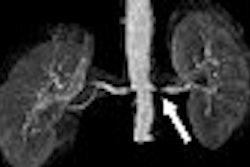

"The MRI relaxation parameters T2 and T2* have been used to infer cardiac iron loading in patients with thalassemia," he added. Low T2* at less than 20 msec suggests high myocardial iron and has been associated with poor ventricular function, myocardial arrhythmias, and need for cardiac medications, Wood stated.

Subjects at both institutions had assessment of cardiac T2* and cardiac function on a 1.5-tesla scanner (Signa CVi, GE Healthcare, Chalfont St. Giles, U.K.). Patients at CHLA also underwent MRI-based liver iron measurements. Wood's group stated in their abstract that measuring iron load is an off-label use of MRI.

According to the results based on 18 of 30 patients, the median cardiac T2* was 30.2 and ranged from 3.4 to 72.8. The baseline average MRI T2* for these patients was about 9 msec. After six months of treatment with 30-40 mg/kg/day, the average MRI T2* was 1.8 msec, a decrease of 14.2%.

Wood said that 14 of the 18 patients evaluated showed a decrease in cardiac iron with deferasirox. Cardiac iron levels also decreased by 22.9% from about 18 mg/g dry weight (DW) to 15 mg/g DW. No drug-related serious adverse events were reported among the 15 patients who were available for follow-up evaluation, Wood said.